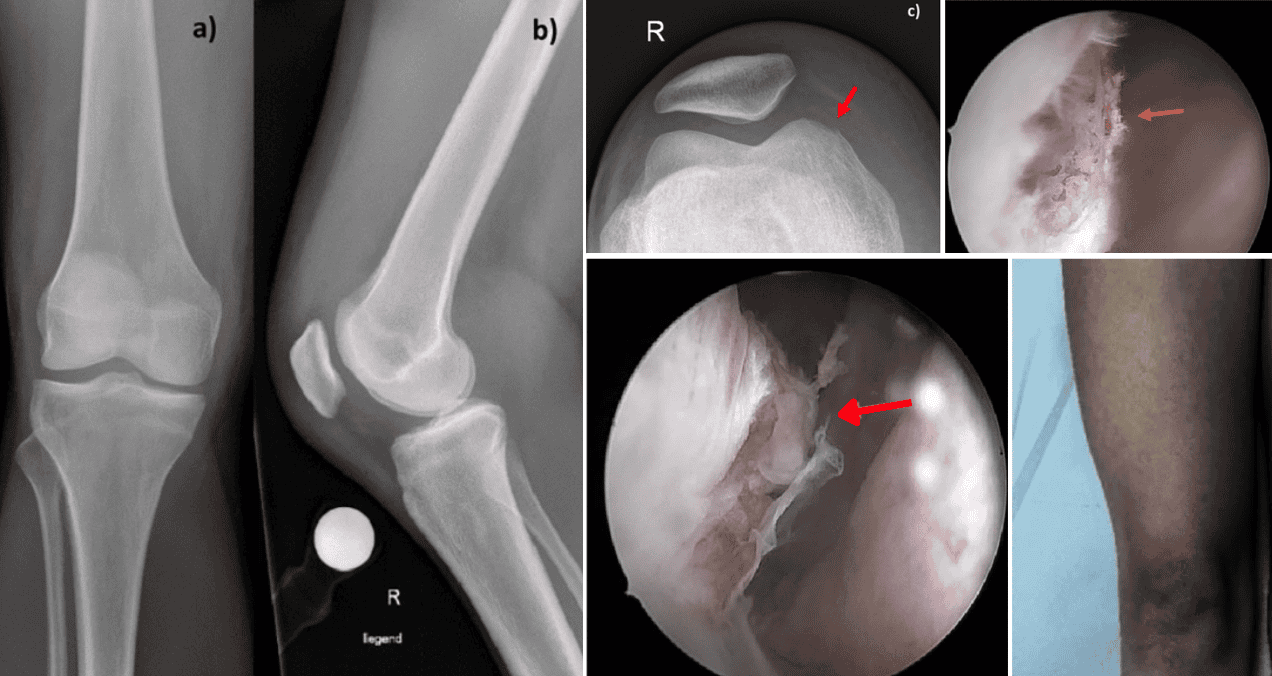

La imagen muestra una vista intraartroscópica del borde del cóndilo femoral medial. La flecha roja señala la fractura en la lesión del cóndilo femoral medial derecho antes del desbridamiento.

La imagen intraartroscópica muestra la correlación de la lesión cutánea externa y la lesión del cóndilo femoral medial con una varilla metálica recta.

Primero, una intervención quirúrgica urgente mediante artroscopia, donde los cirujanos limpiaron meticulosamente la articulación, lavándola con varios litros de solución salina y eliminando todo el tejido inflamado.

Durante esta intervención pudieron comprobar cómo la herida del picotazo efectivamente comunicaba con el interior de la articulación, confirmando la vía de entrada de la infección.